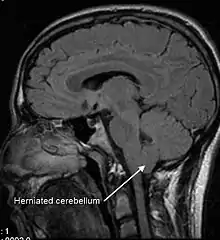

Arnold-Chiari malformasyonu, Chiari malformasyonlarının II. tipidir. Serebellumun büyük bölümü, beyin sapı ve 4.ventrikülün medüller kanala doğru inmiştir. Spina bifida, myelomeningosel ve hidrosefalus ile birlikte görülür. Chiari malformasyonlarının en sık görülen tipidir. Multifaktöryel faktörlerin etkileri sonucu oluşan ya da snedroma-özgü bir bulgu olarak saptanan malformasyonlardır. 2 yaşından küçük çocuklarda beyin sapı ve kraniyal sinirlerle ilgili belirtilerle ortaya çıkar. Çocukluk döneminde yaşamsal belirtilerle ortaya çıkar; sorunların giderilmesi için cerrahi girişimler gerekir.[1][2]

Kafatası içi boyutlarında küçüktür (özellikle kafa tabanı ve arka çukur). Serebellum küçüktür ve alt bölümü (serebellar tonsiller) foramen magnum’a fıtıklaşır. Ventriküllerde deformasyon oluşur. Kafatası sinirleri etkilenmeleri 5 duyuda sorunlara neden olur. Cisterna magna olarak bilinen beyin-omurilik sıvısı deposu oluşmamıştır. Hidrosefalus saptanır.[3]

Hidrosefalus vardır, serebellumun alt bölümü (serebellar tonsiller) foramen magnum’dan omurilik kanalına doğru itilmiştir. Olguların çoğuna siringomyeli eşlik eder. Klinik belirtiler (kas güçsüzlüğü, başağrısı, görme ve kulak sorunları, serebellar ataksi, vd) 20 yaşlarında ya da daha geç dönemlerde ortaya çıkar. Skolyoz ya da kifoz eşlik edebilir. Klinik bulgular genellikle 25 yaşlarında belirir. Olguların çoğu belirti vermez (travma ve gebelik tetikleyici olabilir).[4][5]